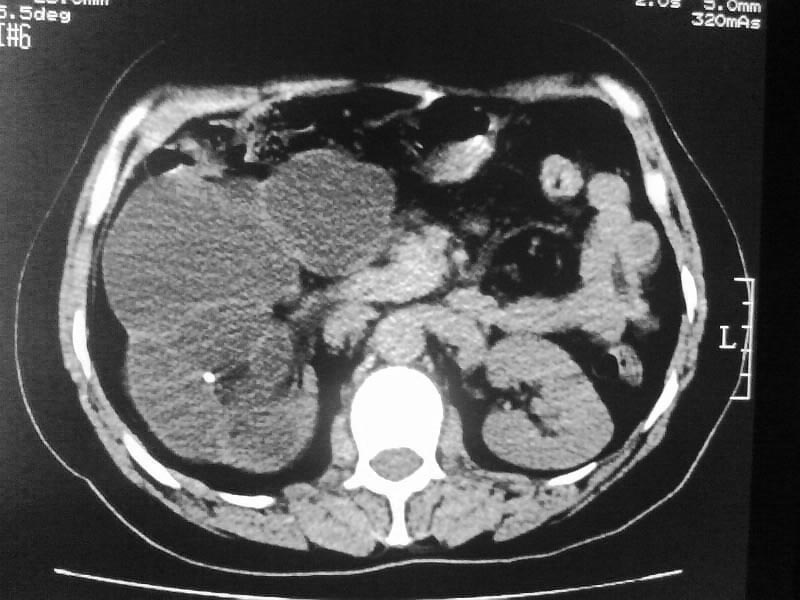

标题: CT20044:女,45岁,腰痛2年,双肾结石,右输尿管结石,右肾重度积 [打印本页]

标题: CT20044:女,45岁,腰痛2年,双肾结石,右输尿管结石,右肾重度积

其内见多房性分隔考虑多囊肾

不像普通的积水,密度像是积脓;

多囊肾可以排除。

支持双肾结石、右输尿管上端结石,右肾重度积水

支持 右肾结石、右输尿管上端结石,右肾重度积水。

双肾结石、双输尿管结石并右肾积水。